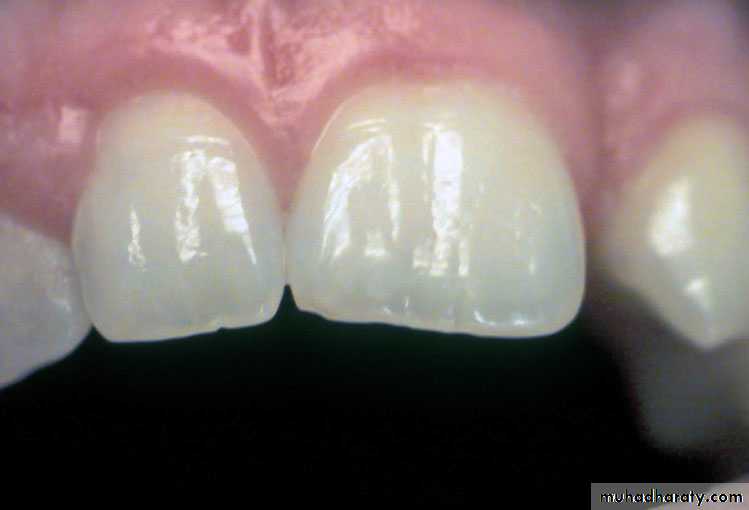

Fusion of a permanent central and lateral incisor

Gemination

Germination is a dental phenomenon where a developing tooth splits in to two separate teeth, it is seen in both primary and permanent teeth, though it probably appears more frequently in primary teeth.

The phenomenon of germination arises when two teeth develop from one tooth germ and, as a result the patient has a larger tooth but a normal number of teeth overall, in contrast to fusion, where the patient would appear to be missing one tooth.